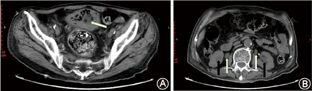

经全院会诊后给予积极监测并控制血糖;尿细菌培养结果提示大肠埃希菌感染,根据药敏结果将抗生素更换为美罗培南抗感染治疗;导尿管持续开放,保证尿液引流通畅;予补钾支持治疗。经上述治疗3 d后,复查血常规示白细胞9.8×109/L,中性粒细胞0.760;血生化示尿素氮8.47 mmol/L,肌酐70.3 μmol/L,钾3.62 mmol/L,各项指标较治疗前明显好转。复查腹盆部CT平扫:膀胱壁内及腔内气体较前明显减少,双侧肾输尿管积水扩张较治疗前明显减轻(图2)。嘱患者院外口服敏感抗生素治疗并控制血糖,出院1周后复查上述实验室检查指标均恢复正常,嘱患者拔除尿管后规律口服治疗前列腺增生的药物,改善患者排尿症状,以预防本病的复发。出院后1个月,电话随访,患者无不适症状,未再就诊。